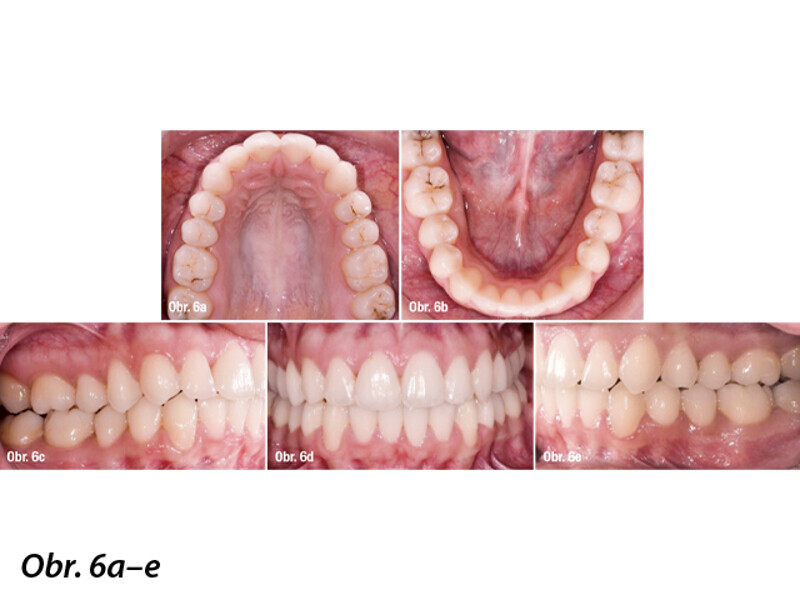

Ortodontická léčba komplexních případů malokluze pomocí průhledných alignerů